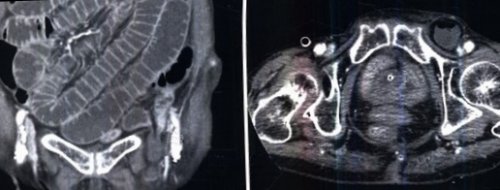

Подготовка к исследованию КТ малого таза

Подготовка к исследованию КТ брюшной полости:

Подготовка к КТ почек и мочеточников